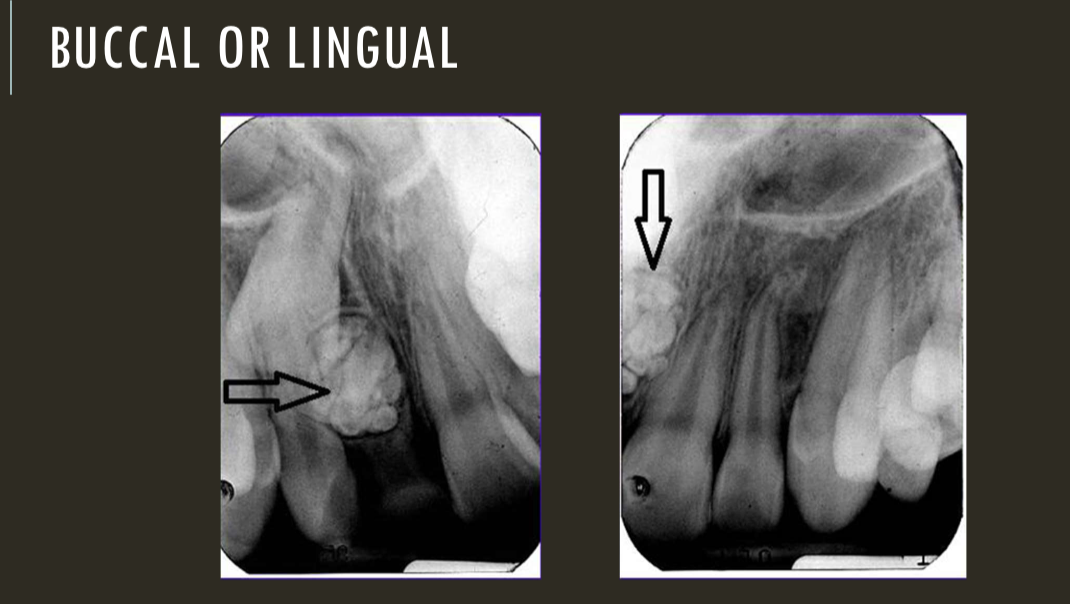

buccal object rule

expose 1st image (PA or bw)

take a second image with a different H or V angulation aka same area different angle

compare images to see how the object shifted in the image

SLOB

lingual

right angle technique

buccal

lingual

lingual

buccal

unable to assess from this single image the objects buccal-lingual position relative to the teeth